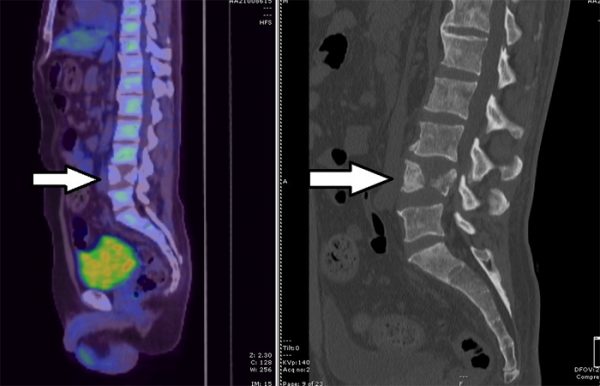

我心里怀疑是癌细胞转移到脊椎,给德瑞克扫描后,发现他的第四节脊柱出现压缩性骨折,局部碎骨塌陷,压制后方的神经线,引发剧烈的坐骨神经痛,站立时痛感尤甚,平躺时则得以舒缓。

我在德瑞克的第三节腰椎至骶骨进行了融合手术,置入6枚钛合金螺丝,固定和支撑塌陷的脊椎。脊椎的压迫解除了,坐骨神经痛也迎刃而解。